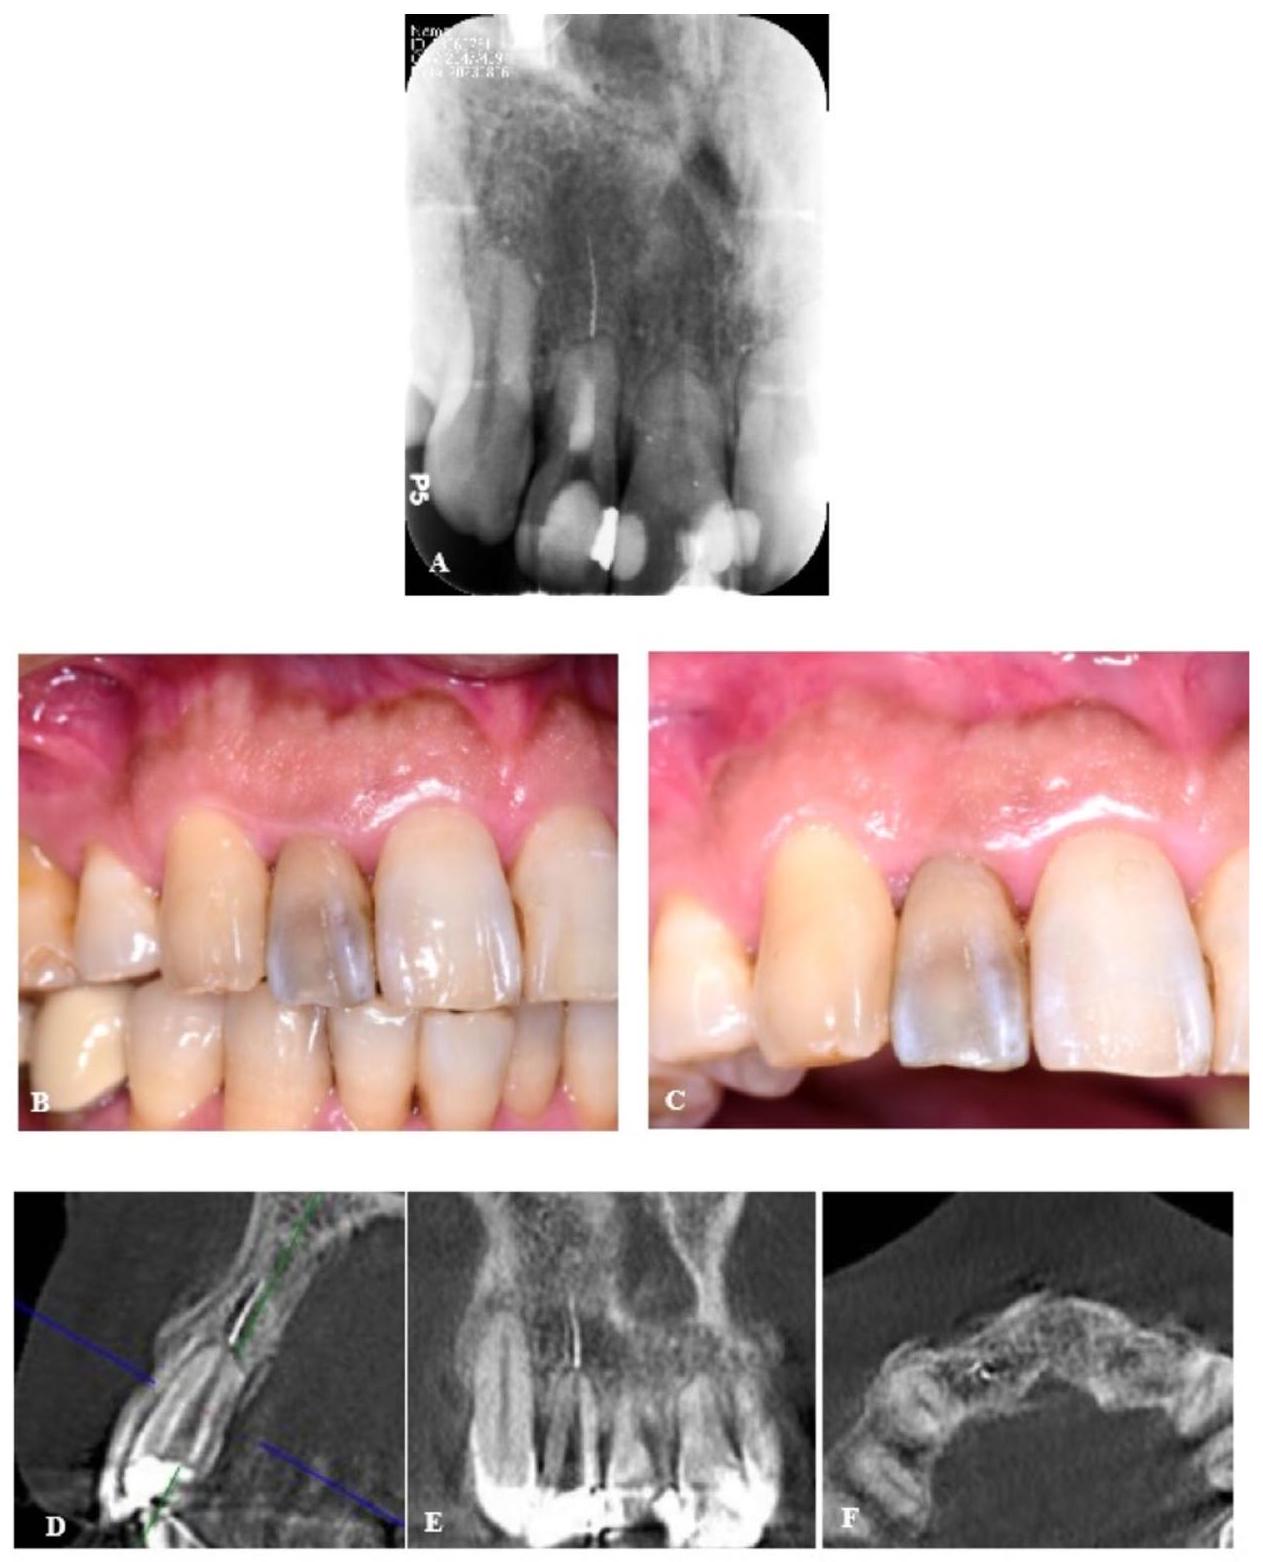

إزالة أداة مكسورة خارج الفتحة الذروية باستخدام جراحة الميكروسكوب السنية بمساعدة الروبوت: تقرير سريري Removal of a fractured file beyond the apical foramen using robot-assisted endodontic microsurgery: a clinical report

خلفية: تعتبر كسور أدوات العلاج الجذري من المضاعفات الشائعة لعلاج قناة الجذر، وتتطلب الإزالة عبر تقنيات متخصصة مثل جراحة الميكروسكوب السنية عندما يكون الملف قد تجاوز الفتحة القمية. غالبًا ما يكون من الصعب إزالة ملف مكسور بدقة وبأقل تدخل. مؤخرًا، أظهر استخدام نظام الروبوت المستقل للأسنان (ATR) وعدًا في إجراء الجراحة السنية بدقة وبأقل تدخل.…